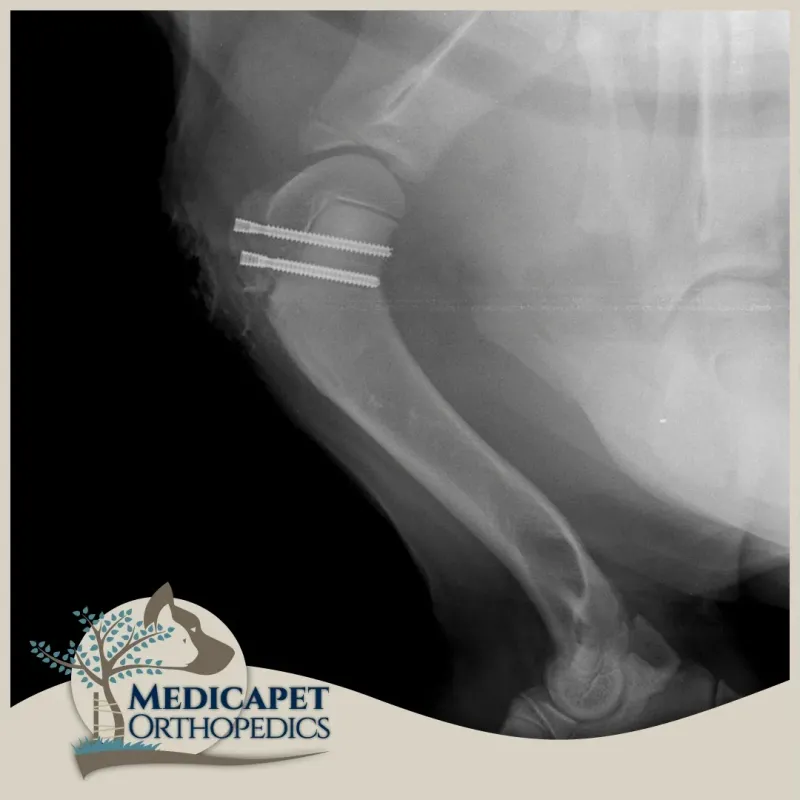

Omuz instabilitesinin tedavisi, burkulma ve zorlanma derecesine ve instabilite derecesine bağlıdır. Düşük dereceli yaralanmalar genellikle anti-inflamatuar ilaçlar, egzersiz modifikasyonu, fizyoterapi ve hidroterapi ile cerrahi olmayan bir şekilde tedavi edilir. Yüksek dereceli yaralanmalar ise stabilizasyon, omuz füzyonu veya total omuz replasmanı kullanılarak tedavi edilebilir.

omuz-instabilitesi-3